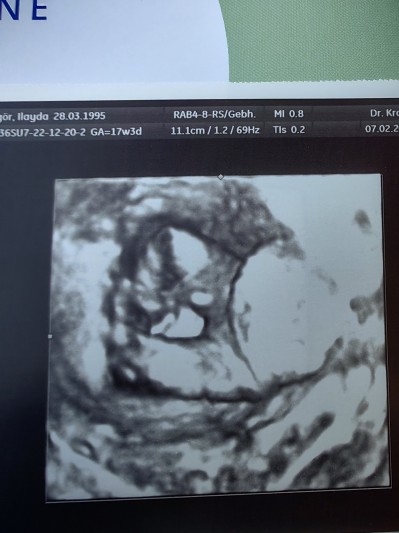

Doktoruma cinsiyet öğrenmek istiyorum deyince, 3D resmini verdi bacak arasıymış. Söylemedi kendisi. Kendin bulabilirsin ne olduğunu dedi dalga geçer gibi :(

Kız benziyor sanki ya o nasıl doktormus kendim bulsam size niye sorayım yani ne cins insanlar var

Kıza benziyor,pipi yok

Bacak arası boş kız bence

Ne kadar saçma bir cevap vermiş ben 12. Haftamda öğrendim doktor erkeğe benziyor dedi ama 1 ay sonra net belli olur dedi gobek kordonu da olabilir dedi 16. Haftamda gittim tam belli oldu yani ne kadar saçma bir şey benim doktorumda 3 D resmini verdi ama bacak arası değildi yüzüydü herkes kız demiş ama ben orada bir çıkıntı gördüm biraz parlamis açıdan dolayı boş gözüküyor ama bence erkek sağlıklı gelsinde de hayırlısı olsun inşallah

Erkek canım Allah bağışlasın pipisi var orda

Teşekkür ederim yorumunuz için, orası bacağın üstün de sanki diye kordon olabilir diye düşünmüştüm :)